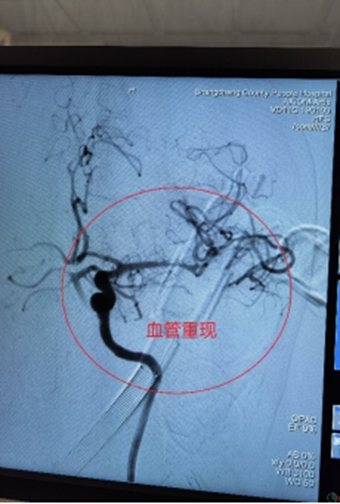

1、左侧颈内动脉末端闭塞,急诊导管抽栓+支架拉栓1例;

0009.jpg

0010.jpg

0011.jpg

0012.jpg